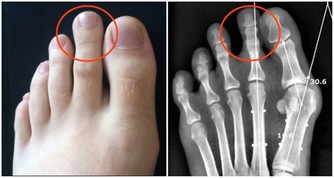

腫瘤部位不同,症狀也不同

同是大腸癌病友,但每個人的情況也會不一樣。

這是因為,長在不同部位的腫瘤,表現出來的症狀不一樣。